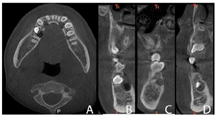

。CBCT示11牙根向远中明显弯曲,牙根发育至Nolla9期;21牙根发育至Nolla9期,腭侧见两颗正置锥形多生牙,牙根未发育完成;12、22牙根发育至Nolla9期;23牙冠近中倾斜至62根方。

根尖片示:11自根中向远中弯曲约35°,属Ⅱ类弯曲牙,牙根发育至Nolla9期,21牙根发育至Nolla9期,腭侧见两颗正置锥形多生牙;12、22牙根发育至Nolla9期。

CBCT示:上颌恒牙胚萌出间隙不足,根据Moyers混合牙列分析法,牙弓现有长度为177.4 mm,牙弓应用长度为181.6 mm,拥挤度为4.2 mm。42缺失;11、21、22发育至Nolla9期;55、16、65、46冠部低密度影及牙本质中层,根管内未见高密度充填影,根尖周未见明显异常。53、63牙根吸收不足1/3,13、23发育至Nolla8期。

2020年12月21日口腔颌面部CBCT精确定位、笑气镇静+4%肾上腺素-盐酸阿替卡因注射液局部浸润麻醉下先行拔出恒中切牙腭侧多生牙,同期切除部分牙龈暴露双侧上中切牙牙冠最宽径。4个月后11仍未有萌出迹象,21萌出,与31反

患者初诊时根据恒牙发育Nolla分期诊断该患者11、21、22迟萌,其可能原因与腭侧多生牙、11牙根弯曲及可能患有颅骨锁骨发育不全综合征相关。

本例患者11属于Ⅱ类弯曲牙,21未见牙根弯曲。对11、21采取早期矫治手段,通过外科开窗助萌开辟患牙萌出间隙,定期其自然萌出情况,必要时利用矫治器牵引患牙使其萌出。该患者于笑气辅助局麻一次性拔除上颌前牙区多生牙后,对11、21进行开窗助萌,观察4个月后因11仍无法自行萌出,因此对其进行正畸牵引,6个月后11完全萌出,并与41形成浅覆牙